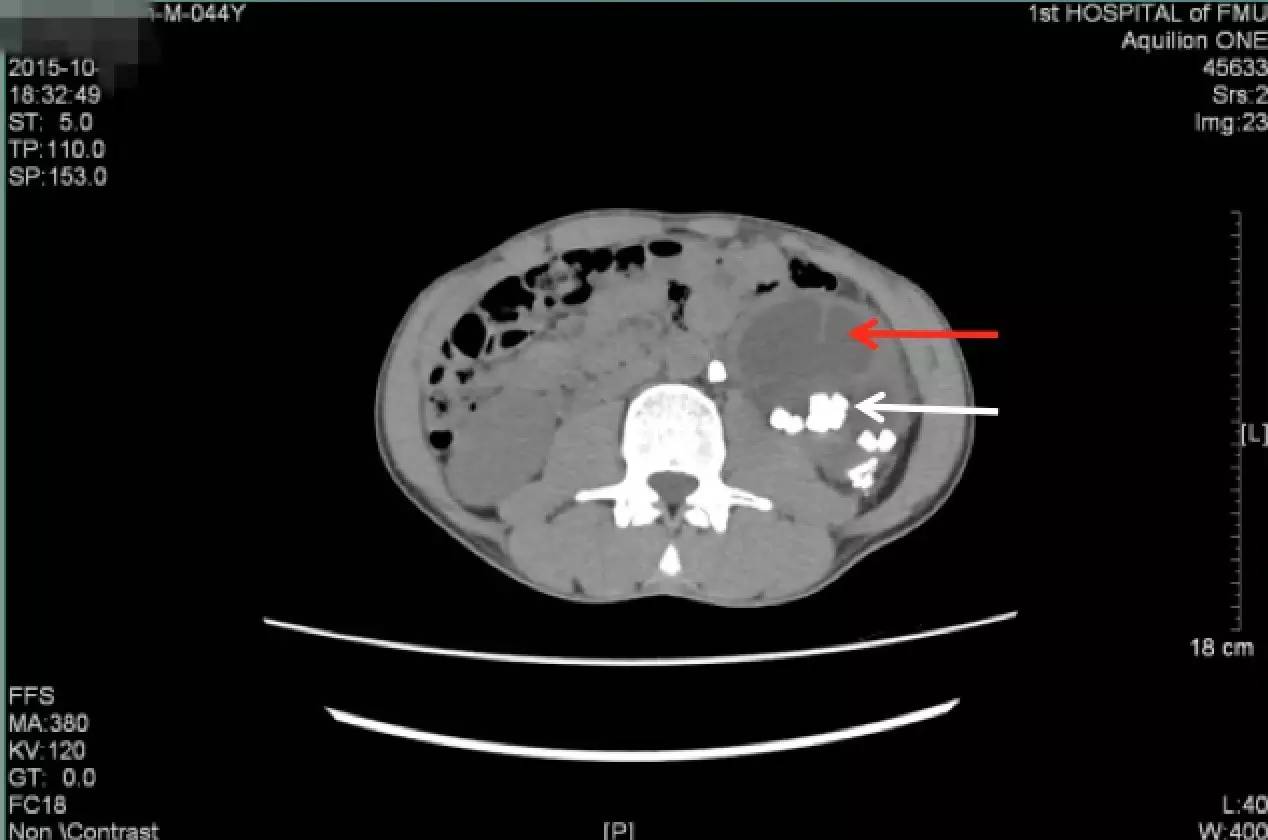

入院后进一步行泌尿系CT平扫+三维重建

(白色箭头提示的就是多发的残留结石)

泌尿系CT:红箭头示左肾重度积水;白箭头示多发结石

白色箭头所指就是引起梗阻的掉到输尿管的结石